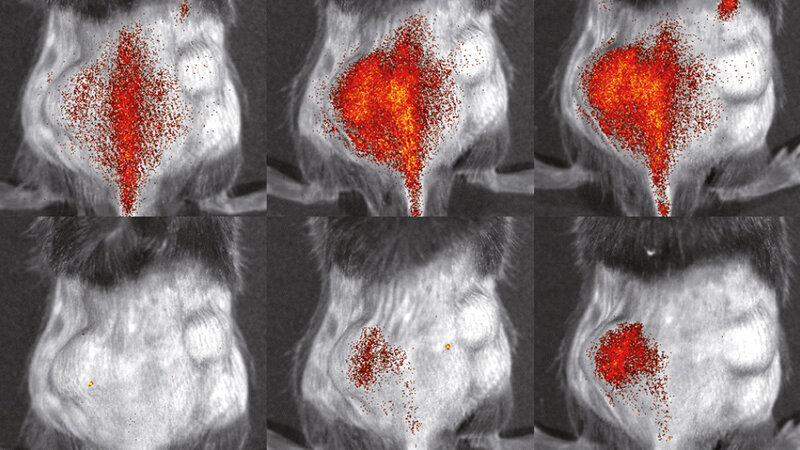

Danach konnten die Bildgebungsspezialisten des Exzellenzclusters die so gewonnenen Zellen mit verschiedenen fluoreszierenden Farbstoffen markieren und sie in lebenden Organismen untersuchen. Sie injizierten Mäusen mit einer entzündungsbedingten Hautkrankheit sowohl mutierte als auch gesunde Immunzellen und konnten so den Weg der Zellen innerhalb desselben Tieres vergleichen. Die Beobachtung fand mithilfe der Fluoreszenz-Reflektions-Bildgebung statt. „Wir konnten sehr genau beobachten, wie unterschiedlich sich die verschiedenen Immunzellen verhielten. Zum Entzündungsherd schafften es etwa doppelt so viele gesunde Immunzellen im Vergleich zu den genetisch veränderten“, sagt Dr. Lisa Honold, ebenfalls federführende Autorin der Studie.

Der nächste Schritt beinhaltete die Beobachtung der wandernden Immunzellen bei Mäusen mit einem Herzinfarkt. Da sich das Herz beim Pumpen schnell bewegt und tief im Körperinneren liegt, stellen solche Beobachtungen naturgemäß eine Herausforderung dar. Mithilfe des nuklearmedizinischen Bildgebungsverfahrens SPECT – Einzelphotonen-Emissions-Tomographie – haben die Forscher digitale Schnittbilder aus tiefen Gewebeschichten erstellt. Noch im Reagenzglas markierten sie die Zellen mit einer radioaktiven Substanz, deren Strahlung gemessen und in Bildern gesehen werden kann. Nach der Injektion in die Mäuse untersuchten sie, wann die Zellen wo während des Herzinfarkts waren. „Durch die serielle Bildgebung können wir nun das Verhalten von Immunzellen über einen langen Zeitraum verfolgen“, erläutert Nuklearmediziner Prof. Dr. Michael Schäfers, Koordinator des Exzellenzclusters. Auch dies soll zu weniger benötigten Versuchstieren führen. Herkömmliche Methoden liefern nur Momentaufnahmen und somit deutlich mehr Experimente.